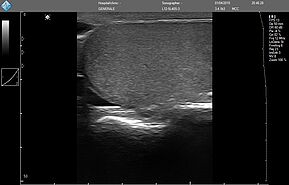

MicrUs Pro - это портативный персональный ультразвуковой сканер, основанный на популярной платформе MicrUs. «Pro» означает «датчик» и «профессионал»: его модернизированная электроника и тщательно разработаны печатные платы обеспечивают качество изображения, оцененное клиентами MicrUs, тогда как размер минимизирован для размещения в корпусе датчика.

Ультразвуковой сканер MicrUs Pro - это идеальное портативное решение для проведения ультразвуковой диагностики в «полевых» условиях, сельской местности, для семейной и военной медицины (ультразвуковое исследование по протоколу FAST* – Focused Assessment with Sonography for Trauma). Особенности этой модели:

MicrUs Pro - это УЗИ устройство, управляемое приложениями, и работает с платформами Windows и Android на современных планшетах и мобильных телефонах. Просто подключите USB-кабель непосредственно к устройству Windows /Android.